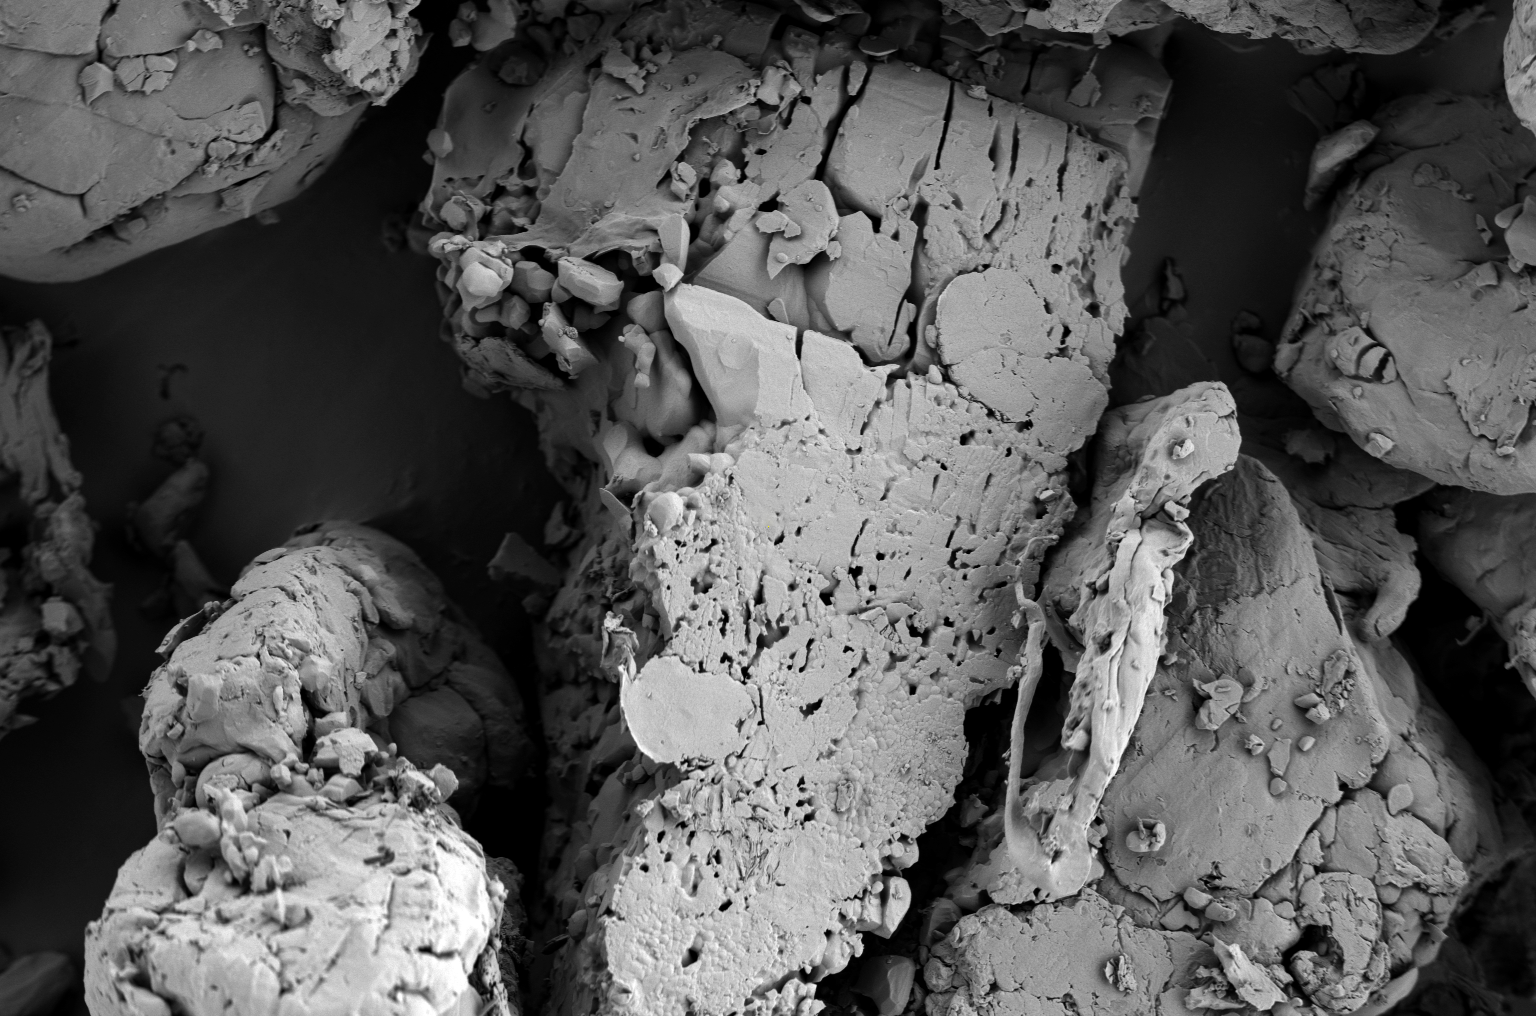

对于复杂制剂体系,如缓控释制剂,扫描电镜能够揭示其内部结构特征与药物释放机理的关联,为制剂设计提供重要依据。比如,氯化钾本身具有典型的立方晶系结构,见图2a。在氯化钾缓释片的研发中,采用羟丙甲纤维素作为亲水凝胶骨架材料。通过扫描电镜观察可见,被粉碎后的氯化钾不规则晶体(仍可见部分立方体轮廓)被HPMC形成的连续凝胶网络紧密包裹和粘合,API与辅料界面结合良好,整体结构致密,内部孔洞稀少,见图2b。这种致密结构显著降低了介质的渗透速率,符合Higuchi模型描述的扩散控制释放机制,其微观结构特征为其缓释机制提供了直接的形态学证据。

图2b 氯化钾缓释片中被粉碎后的氯化钾不规则晶体(仍可见部分立方体轮廓)

被HPMC形成的连续凝胶网络紧密包裹和粘合,

API与辅料界面结合良好,整体结构致密,内部孔洞稀少